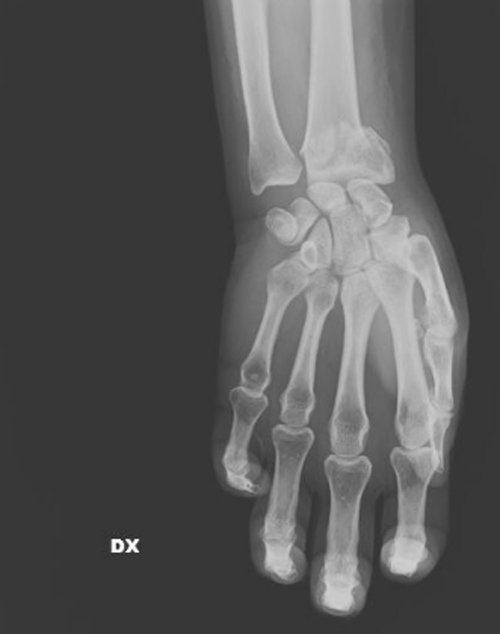

Σπασμένος καρπός/repubblica.it

Όπως σημειώνει η χειρουργός, καθημερινά καλούνται να αντιμετωπίσουν «σπασμένα οστά σε μύτη, χέρια, πόδια, πληγές από μαχαιριές, εγκαύματα, μελανιές και άλλα σημάδια στραγγαλισμού», ενώ σημειώνει πως έχει δεχθεί ασθενή ακόμη και με μαχαίρι στην πλάτη, που όμως το περιστατικό δηλώθηκε ως «ατύχημα» στο νοσοκομείο.